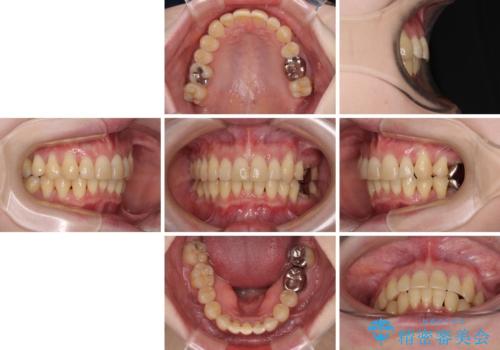

- 八重歯と正中のズレを気にして来院された患者様です。

上顎左側が八重歯になっており、上顎正中が左側にずれていました。

上顎左側の第一小臼歯を抜歯し、補助装置を用いて正中位置を改善しながら八重歯を解消していくこととしました。

下顎前歯が1本欠損していたため、上下正中の位置が合わせるという目標はなく、鼻筋に上顎正中を合わせていくように移動を行いました。